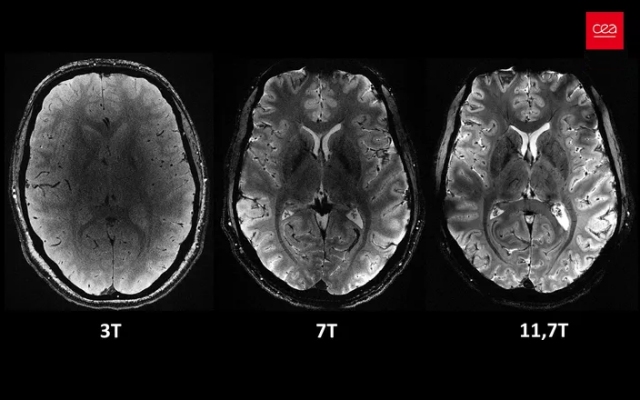

The Iseult MRI scanner, developed in Paris-Saclay by the Atomic Energy Commission (CEA), is the most powerful in the world. Equipped with an unrivaled magnetic field of 11.7 Tesla, it greatly outperforms traditional hospital MRIs (1.5 or 3 Tesla).

The images obtained by Iseult are of exceptional precision, revealing anatomical details unattainable at lower magnetic fields. Healthy volunteers were scanned in this 132-ton magnet, with no adverse effects on their health. This major advance in neuroscience opens new perspectives for research and understanding of neurodegenerative and psychiatric diseases.